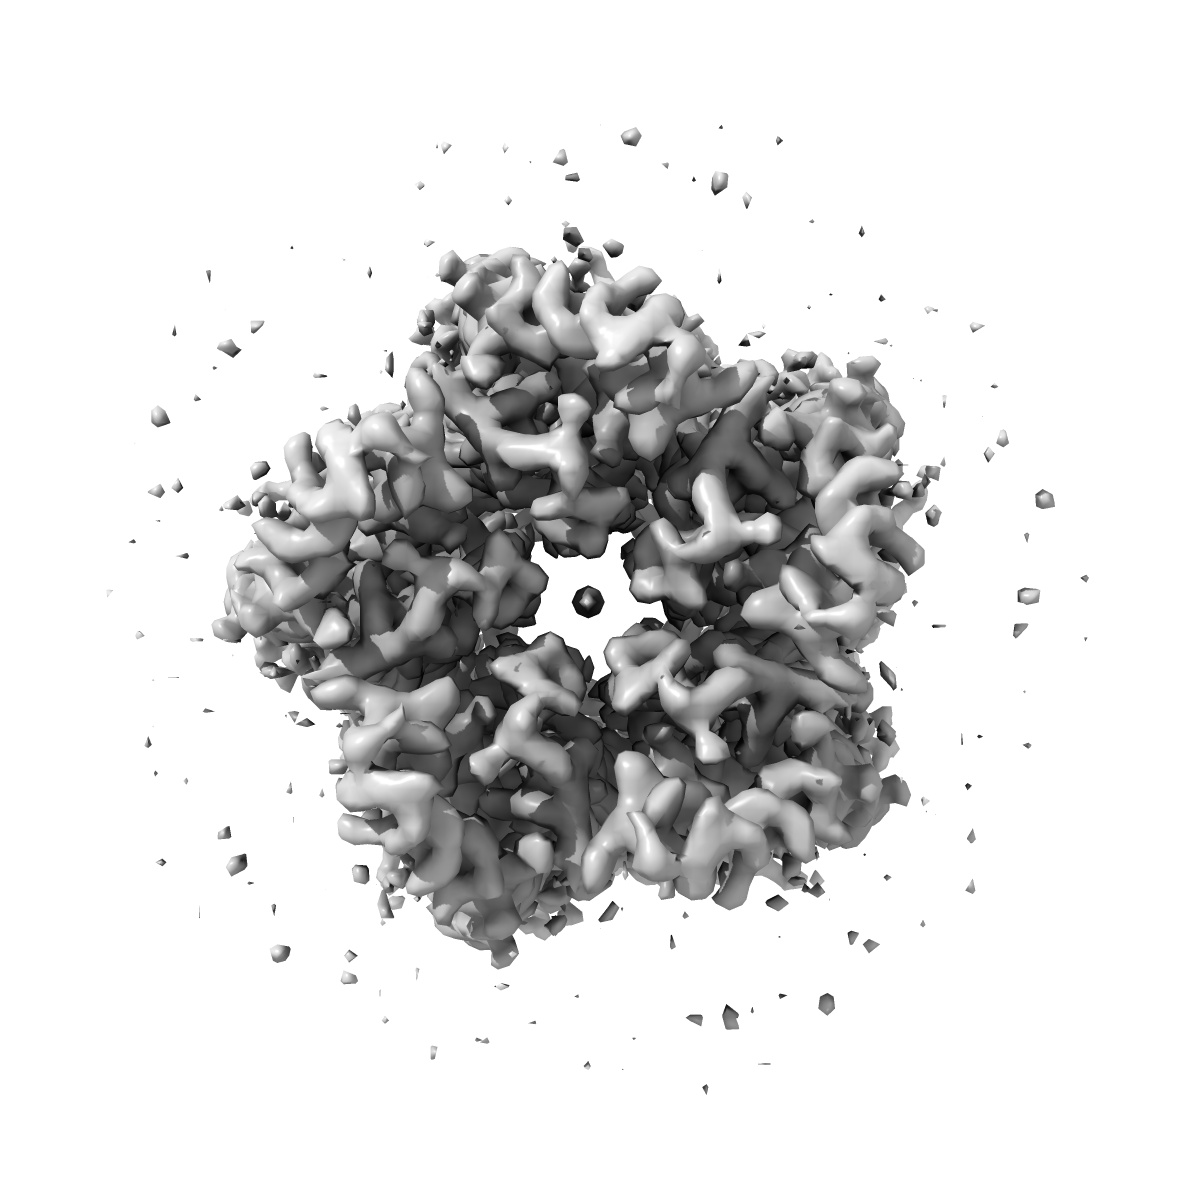

EMD-16067

GABA-A receptor a5 homomer - a5V3 - RO7015738

Single-particle3.38 Å

Sample: GABA-A a5 subunit of homopentamer complex called a5V3

The molecular basis of drug selectivity for alpha 5 subunit-containing GABA A receptors.

(2023) Nat Struct Mol Biol , 30 , 1936 - 1946